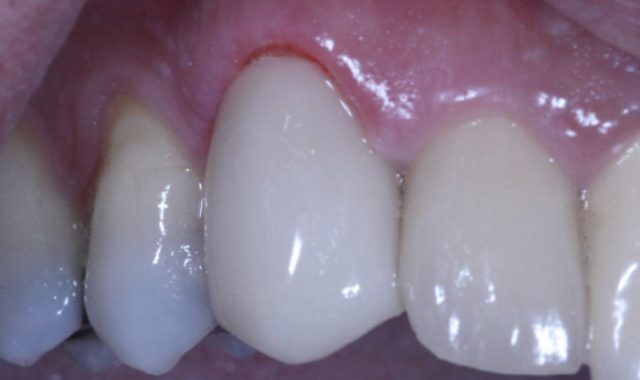

The restoration was seated (Figs. 10-11), contacts and occlusion checked, and luted into place with Ivoclar Vivadent SpeedCem composite luting cement.

The final crown (Fig. 18) was seated and cemented with Ivoclar Vivadent SpeedCem cement. The total treatment time for this case was three-and-a-half hours from start to completion.